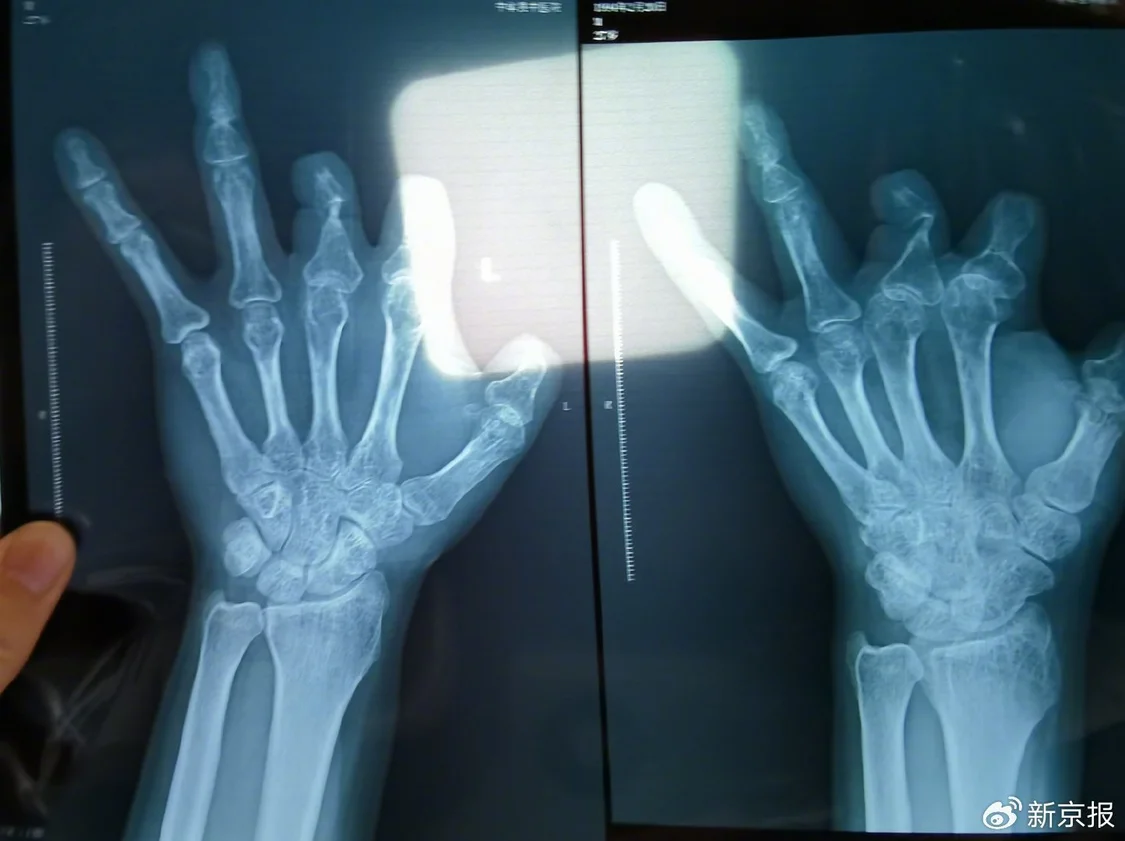

2021年12月,患者彭先生拍摄的左手X光片,未见收费单据中列出的微血管吻合装置。新京报记者 程亚龙 摄

作为一名三甲医院的副主任医师,王福建的所作所为令人瞠目结舌,寒心透顶。医者本应救死扶伤,关怀患者,他却利用患者对医生的信任、对健康的渴求,将手术台变成行骗舞台,把他人病痛当成了敛财机会。根本用不上的昂贵器材,他能一口气给患者开上6个,然后扔进垃圾桶白白浪费。甚至为了规避投诉,他还将本应用于缝合血管的装置,缝在患者血管旁边的肉里,只为在X光下“留痕”。